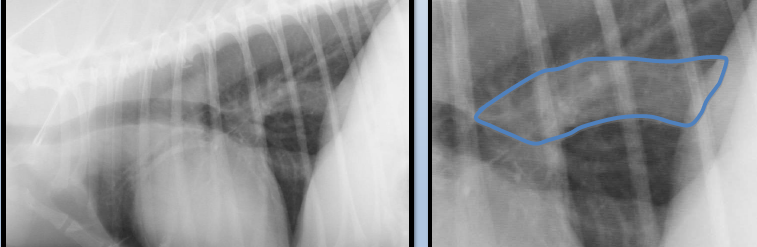

Left atrium